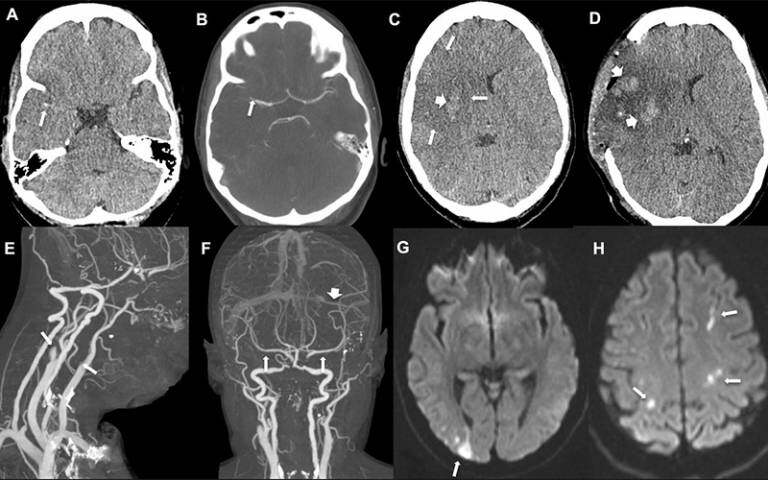

The first patient, a woman in her 30s, experienced an intermittent headache on her right side and around her eyes six days after the vaccine. Five days later she awoke feeling drowsy and with weakness to her left face, arm and leg. Imaging revealed a blocked right middle cerebral artery with brain infarction, and blood clots in the right portal vein thrombosis. She underwent brain surgery to reduce the pressure in her skull, plasma removal and replacement, and received the anti-clotting drug fondaparinux, but unfortunately died.

The second patient, a woman in her late 30s, presented with headache, confusion, weakness in her left arm and loss of vision on her left side 12 days after having received the vaccine. Imaging showed blockages in several vessels including both carotid arteries (the main blood supply to the hemispheres of the brain), arteries supplying the heart and lungs (pulmonary embolism) and the left transverse sinus (one of the cerebral venous sinuses). Her platelet count increased following plasma removal and replacement and intravenous corticosteroids. She was then given fondaparinux and improved.

The third patient, a man in his early 40s, presented three weeks after receiving his vaccination with problems speaking and understanding language (dysphasia). Imaging showed a clot in the left middle cerebral artery, but there was no evidence of clots in the cerebral venous sinuses. He received a platelet transfusion, intravenous immunoglobulins, and fondaparinux, and remains stable.

In all cases, the ischaemic stroke was associated with blockages of large arteries (affecting the carotid or middle cerebral arteries) and two patients also had venous thrombosis involving the portal and cerebral venous system. All three also had extremely low platelet counts, confirmed anti-PF4 antibodies, and raised D-dimer levels – features associated with VIIT.